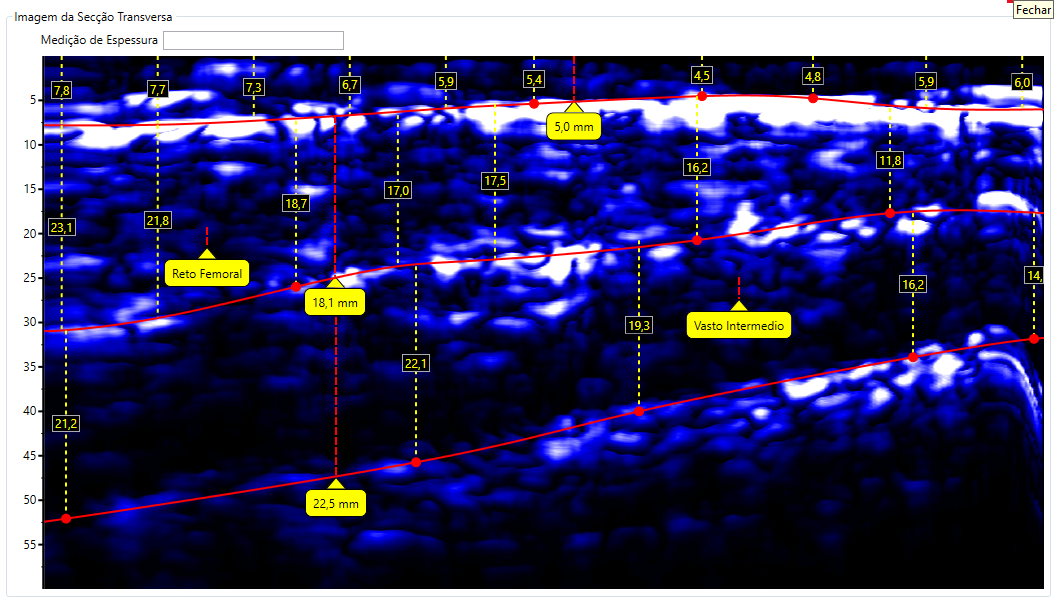

Escaneamento da Coxa